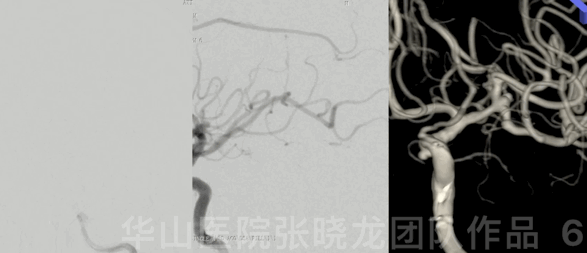

图 3 GIF. 造影证实基底动脉瘤,同时偶然发现肺部血管畸形。

图 6 GIF. DSA证实左侧大脑中动脉分叶状动脉瘤。